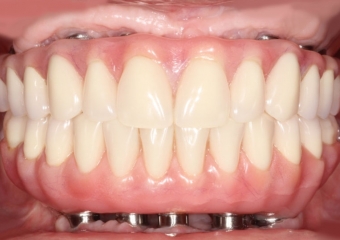

Próteses fixas em resina superior e inferior sobre implantes

Sorriso final do caso terminado em setembro de 2012